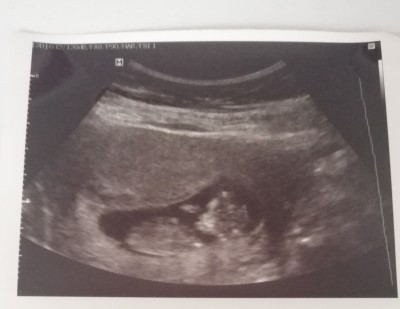

11 haftalığız cinsiyet tahmin edebilen varmıı

Kese fasulye gibiyse erkek oluyomuş. Öyle gözüküyor: ) Allah gönlüne göre versin

Keseye gore degil cunku degisebilir .

Hislerime gore kiz hissettim cnm

Kuyruk sokum kısmı aşağı doğru kız bence öğrenince haber et :angel: